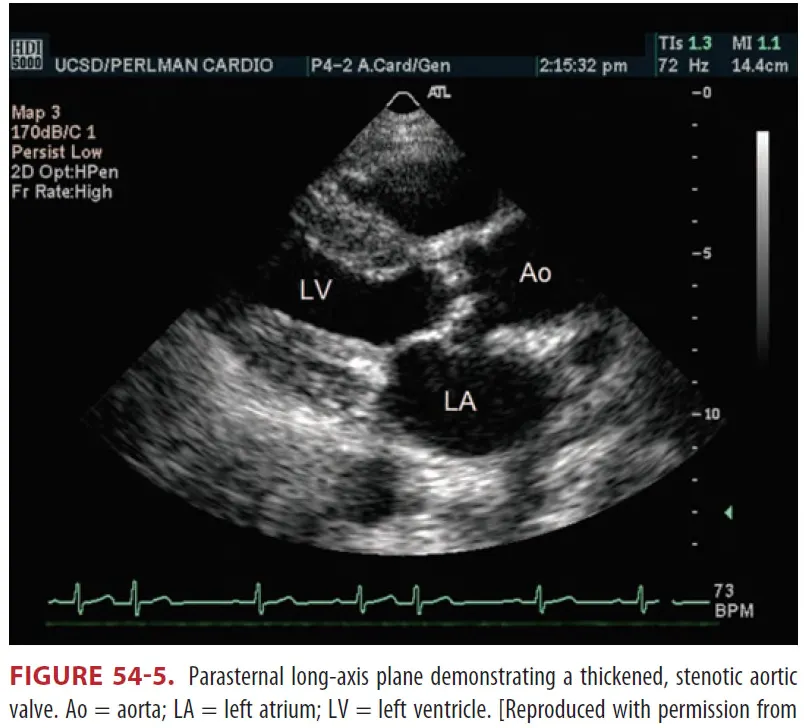

(1) 심초음파

(2) ECG와 Chest x-ray는 민감도와 특이도가 부족